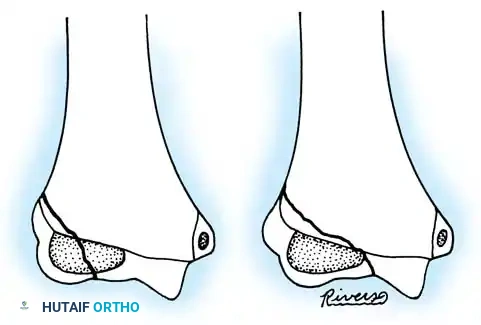

In cases of chronic radial head dislocation (often missed acutely or associated with plastic deformation of the ulna), simple open reduction is insufficient. The Hirayama Technique utilizes an ulnar osteotomy to overcorrect the angular deformity, thereby pulling the radial head back into the joint via the interosseous membrane.

TECHNIQUE 33-5: Osteotomy of the Ulna (Hirayama et al.)

- Preparation: Inflate a pneumatic tourniquet. Make a posterolateral skin incision exposing the radiohumeral joint and proximal third of the ulna. Excise intra-articular scar tissue.

- Osteotomy: Perform a subperiosteal osteotomy of the ulna 5 cm distal to the olecranon.

- Distraction and Angulation: Distract the osteotomy by 1 cm to lengthen the ulna.

- For Anterior Dislocation: Correct by posterior angulation of the ulna.

- For Lateral Dislocation: Correct by medial angulation of the ulna.

- Fixation: Secure the osteotomy with a metal plate bent to approximately 15 degrees. Ensure the radial head rests perfectly within the radial notch of the ulna without excessive radiocapitellar pressure.

- Closure: Approximate the anconeus. Do not repair the annular ligament, as this can restrict rotation.

- Postoperative Care: Apply a plaster splint in 90 degrees of flexion and full supination for 4 weeks, followed by aggressive active range of motion.

Fig. 33-36 Overcorrection with posterior convexity for anterior dislocation.

Fig. 33-37 Overcorrection with medial convexity for lateral dislocation.